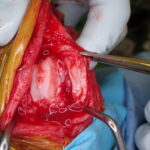

膝蓋骨内方脱臼に対する人工滑車置換術 PGR #23

膝蓋骨内方脱臼に伴い慢性の異常な刺激が進行し、骨関節炎を認め関節軟骨はすでに不可逆的な変性を呈しています。多くの外科手術は”整復”を目的としますが、関節炎が進行した関節においては、単なる整復だけでは痛みや機能障害は残り続けます。そこで必要な手技は”再建”です。損傷した関節面をそのまま使うのではなく、人工滑車(PGR)を用いて新たな滑走面(DLC)を構築することで、関節内の異常なストレスを減少させ、除痛と機能回復を図ります。HAコーティングのベースプレートと骨がオッセオ・インテグレーションを起こすまでは安静が必要です。